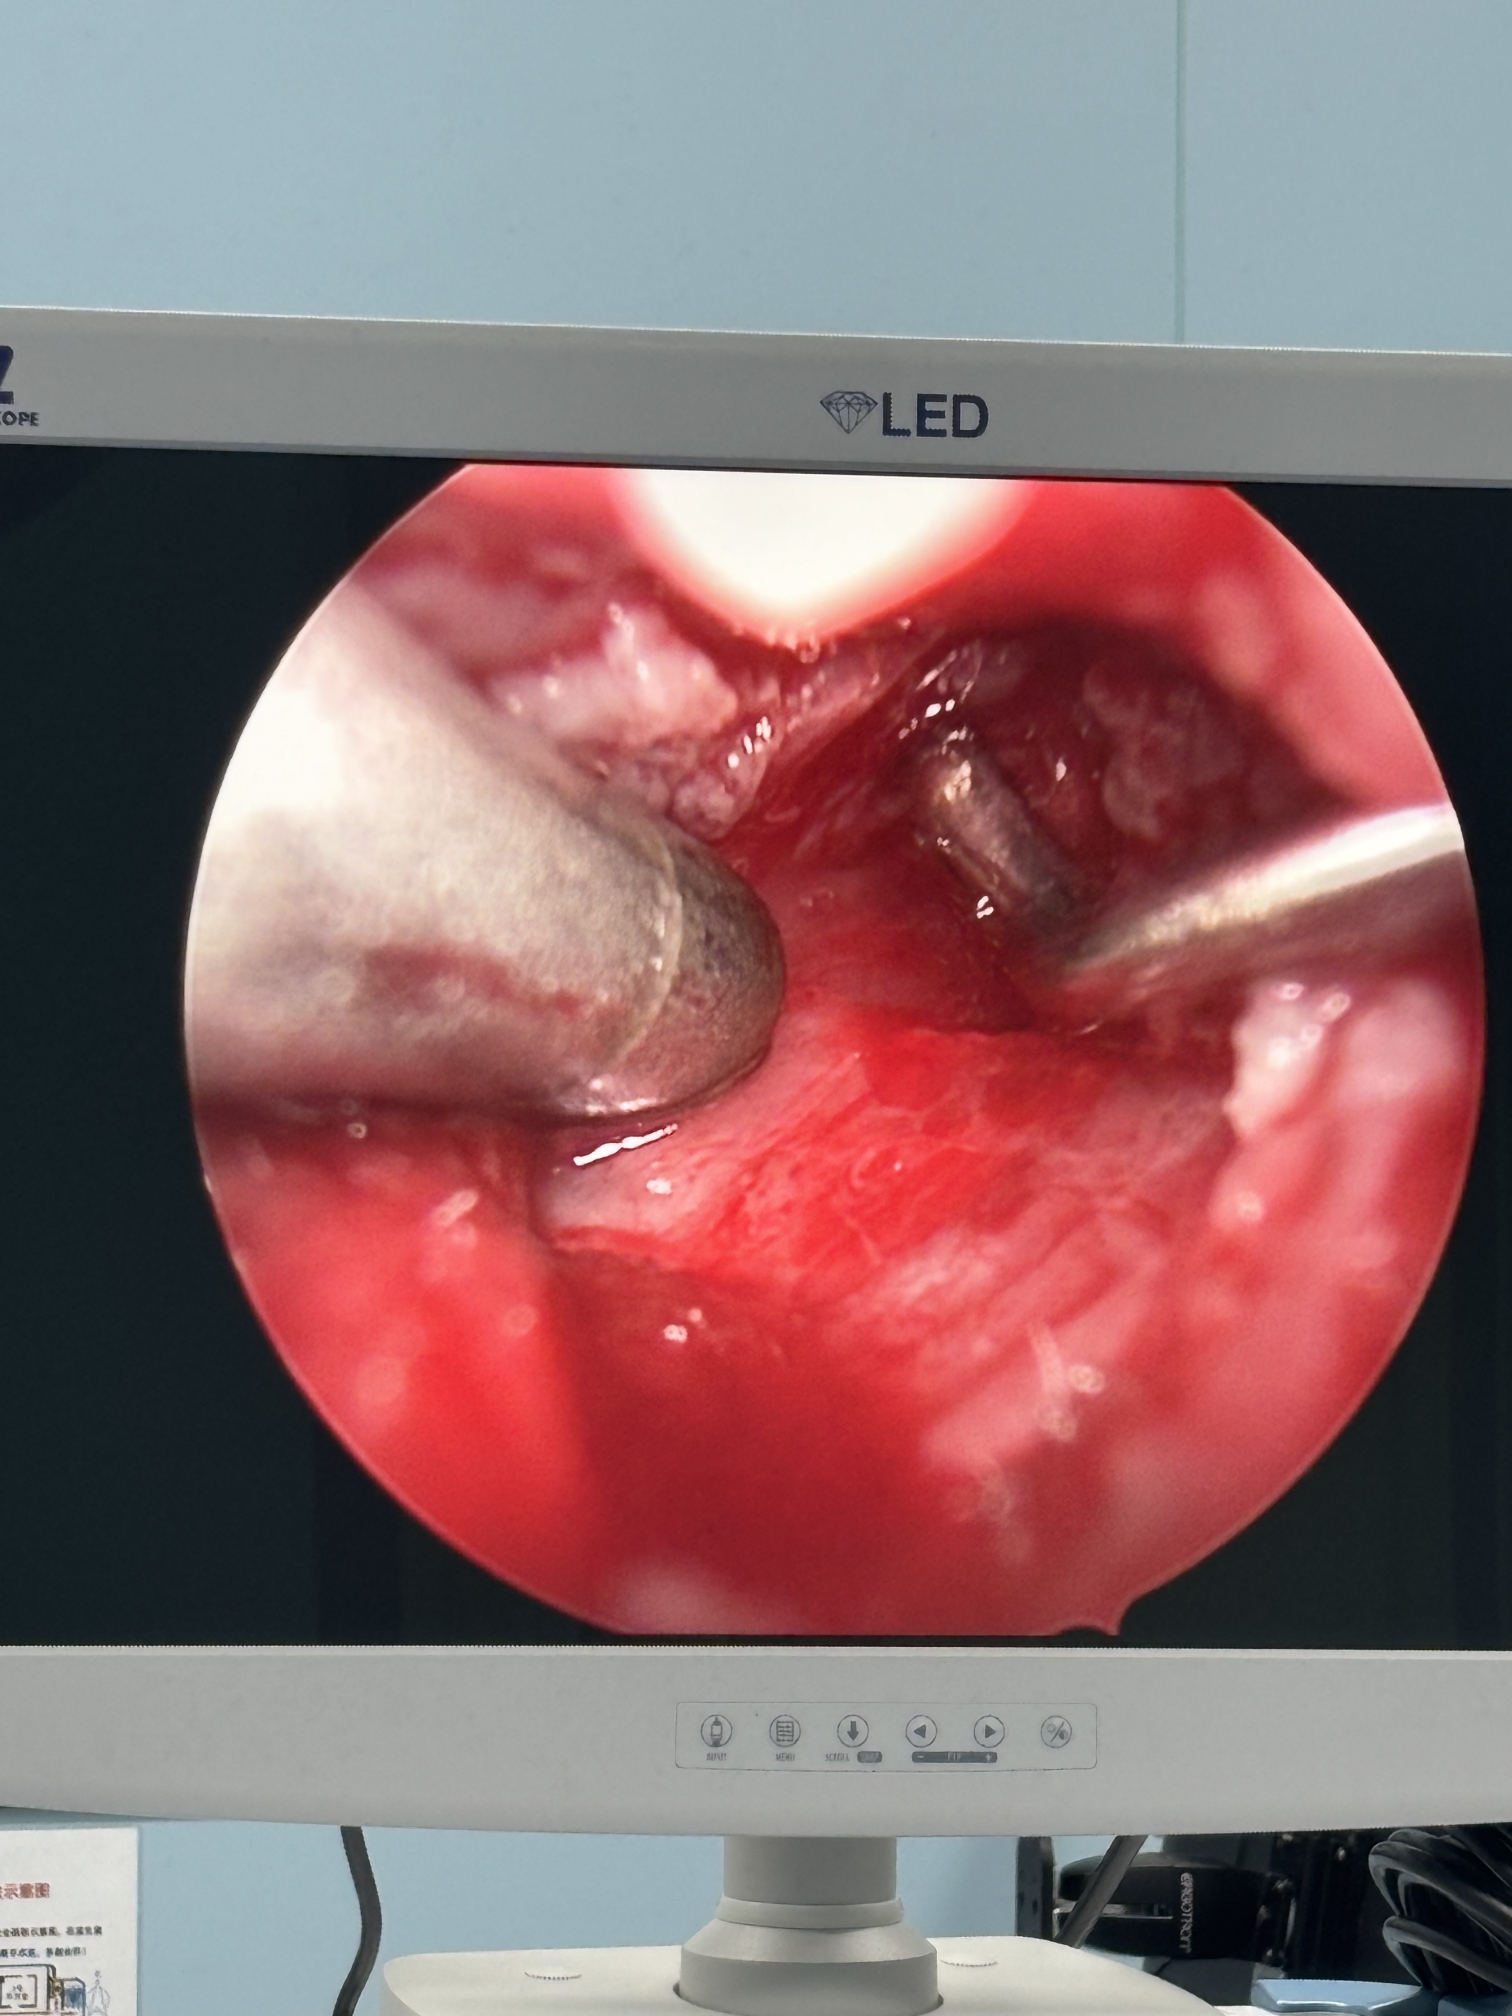

膝关节疼痛,原因是椎管内肿瘤,哑铃型生长,全切肿瘤,保留神经,疼痛症状消失…